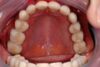

Patientin mit behandelter CMD erhält nach 10 Jahren eine neue vollkeramische Teilkrone

Vor 10 Jahren erhilte die Patientin eine abschließende funktionstherapeutische Rekonstruktion nach mehrjähriger funktioneller Vorbehandlung.

Die Patientin ist bereits seit der Eingliederung der Laborgefertigten Dauerprovisorien, amit über 10 Jahre dokumentiert vollkommen beschwerdefrei!